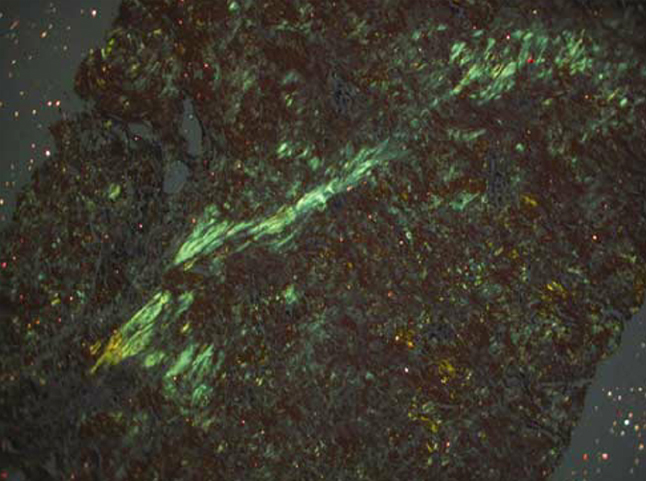

Routine haematological and biochemical profiles were within normal limits. Given the clinical suspicion of a submucosal neoplasm, the patient was taken up for direct laryngoscopy with micro laryngeal excision using CO₂ laser. Meticulous dissection was performed to achieve complete removal of the deposits while preserving the integrity of the vocal ligament and adjacent mucosa. The histopathological examination revealed eosinophilic, amorphous, acellular deposits in the subepithelial stroma (Figure 3). Congo red staining demonstrated classic apple green birefringence under polarized light, confirming the diagnosis of amyloidosis (Figure 4).

Figure 4. Image showing apple green birefringence under polarised light confirming amyloidosis